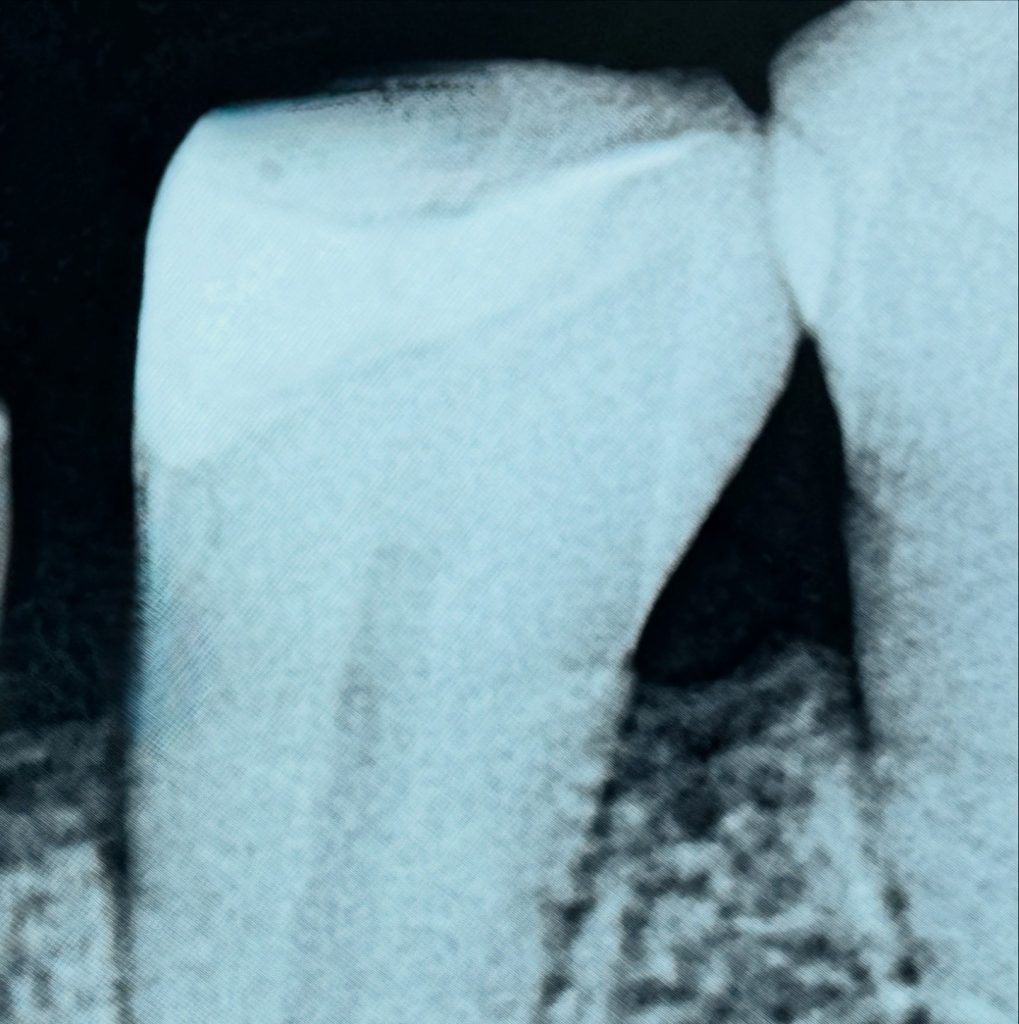

3️⃣ Deep Margin Elevation

A sectional matrix and flowable resin were used to elevate the gingival margin. The “matrix-within-matrix” method provided ideal emergence form and bonding accessibility. (Fig 3)

- Fig 3: Deep-margin elevation using sectional matrix system.